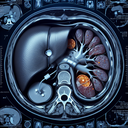

МРТ печінки

Магнітно-резонансна томографія (МРТ) печінки — це неінвазивний метод візуалізації, що дозволяє детально оцінити стан печінки та прилеглих структур. Він використовує магнітні поля і радіочастотні імпульси для створення зображень високої роздільної здатності. ### Основні переваги МРТ печінки: - **Детальні зображення**: Забезпечує високу чіткість та деталізацію тканин...